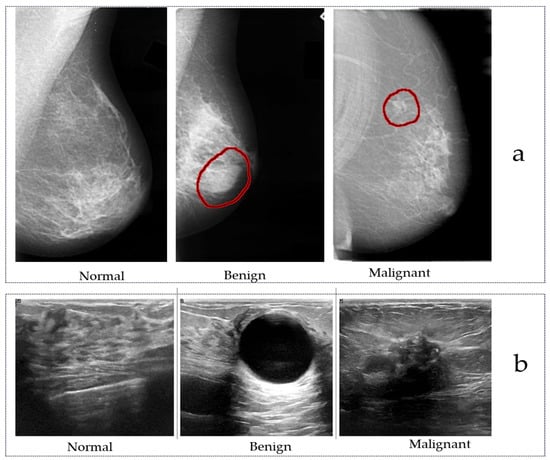

2. Public Breast Cancer Datasets

2.1. Public Mammography Datasets

2.2. Public Ultrasound Datasets